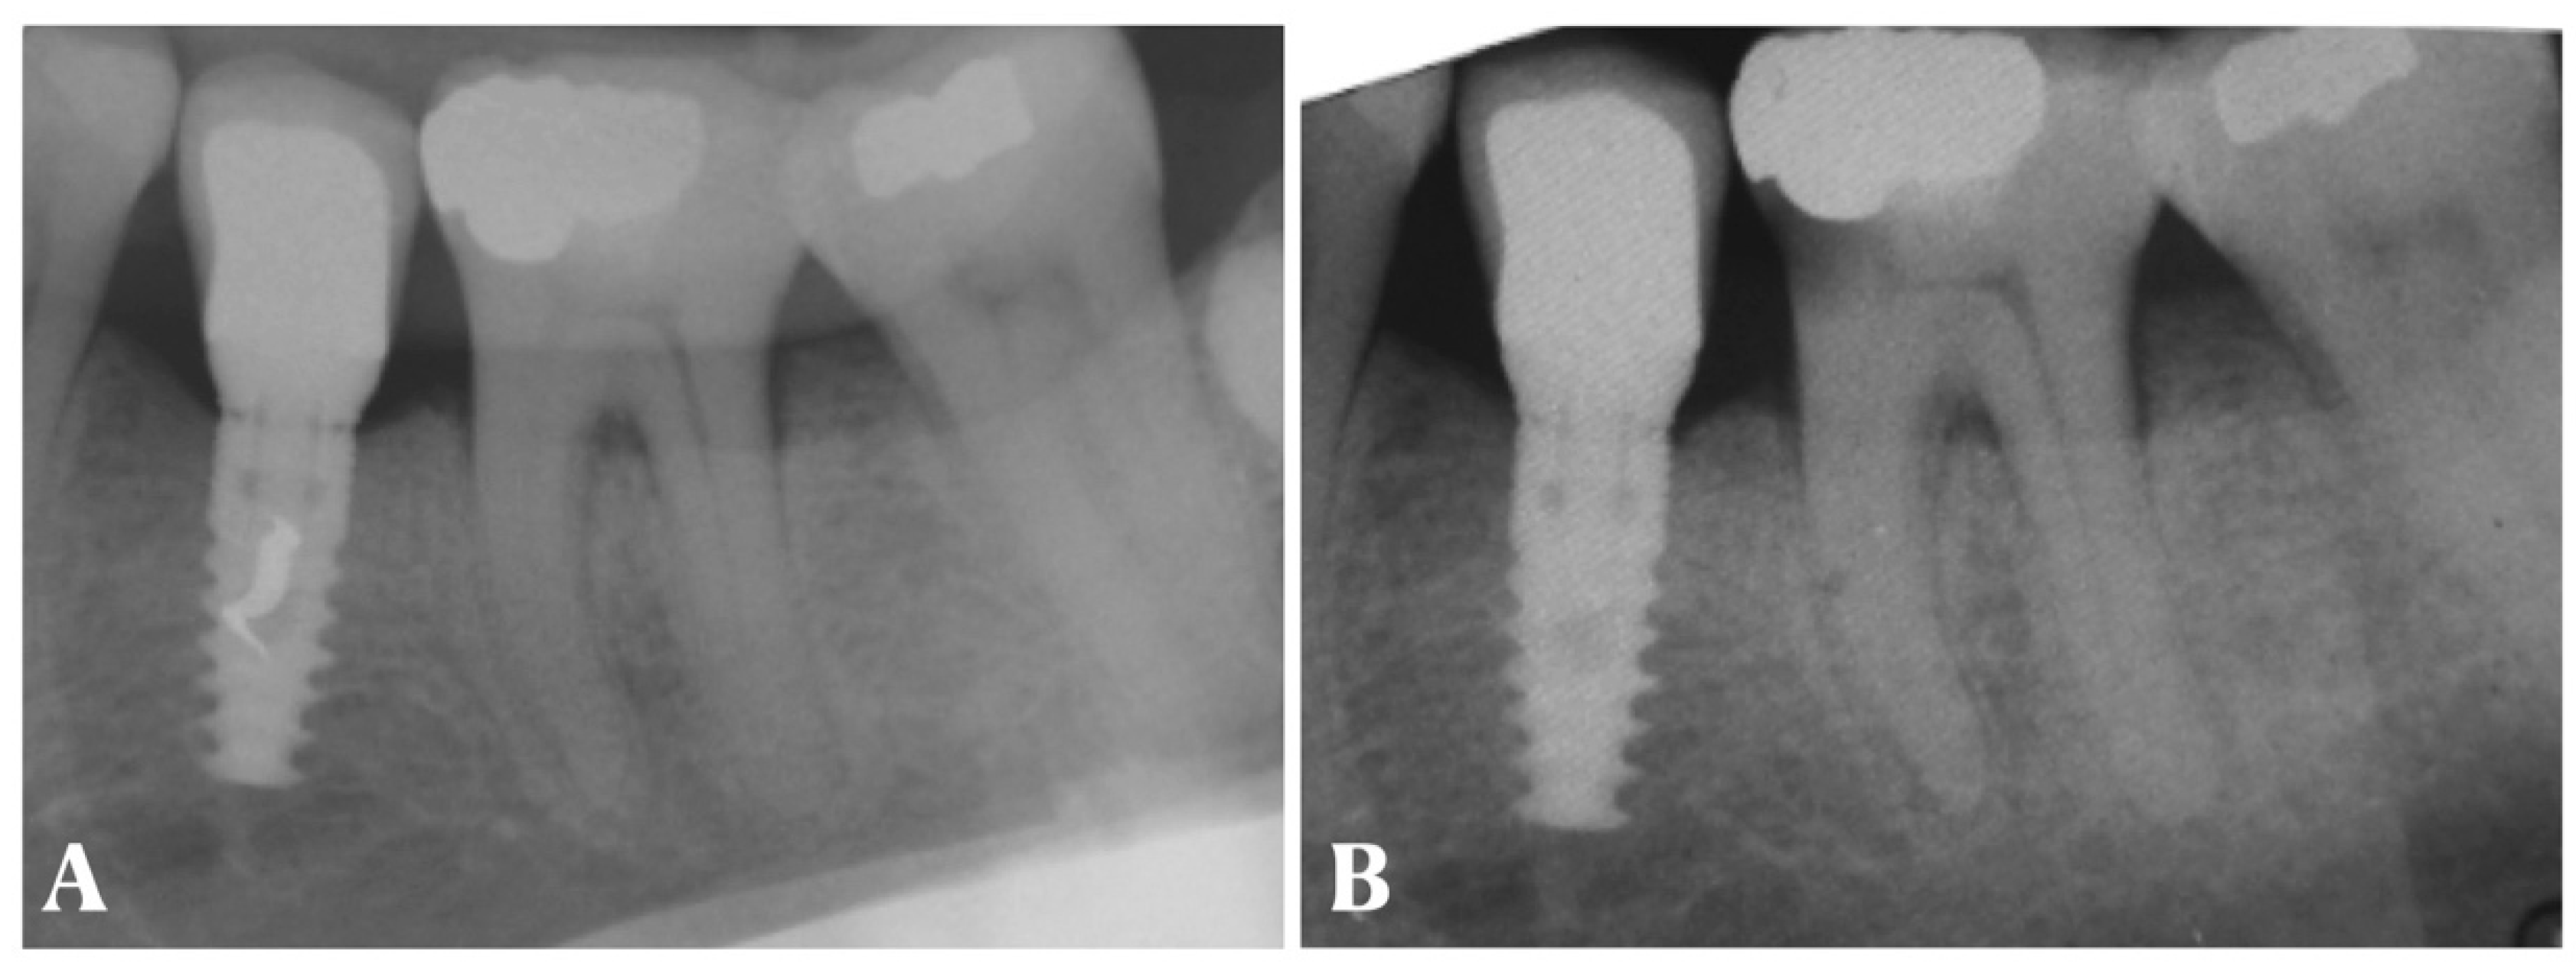

- Periapical X-ray